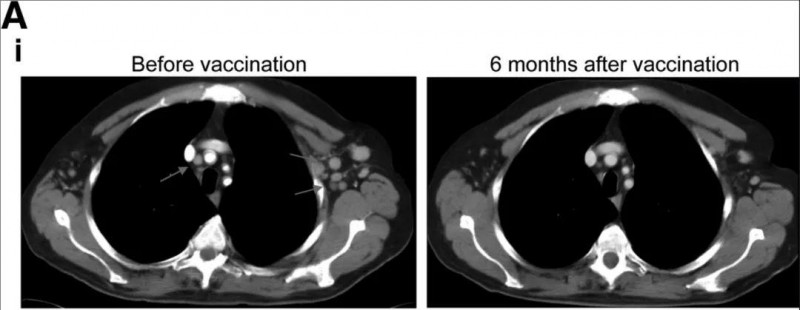

▼12号患者的胸部CT扫描图像

①左图:DC疫苗治疗前的CT图像:该患者存在多个小的肿大的纵隔和左腋窝淋巴结(左,箭头);

②右图:接种DC疫苗6个月后的CT图像:病灶恢复正常。